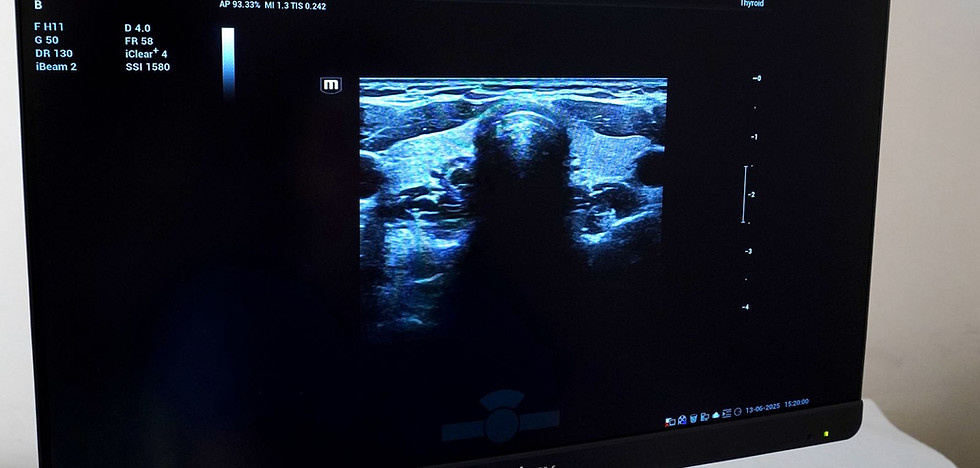

Book your thyroid ultrasound at GI Rimon:

Why undergo this examination?

Ultrasound is a quick, painless, and accurate way to detect nodules, cysts, or structural changes in the thyroid gland.